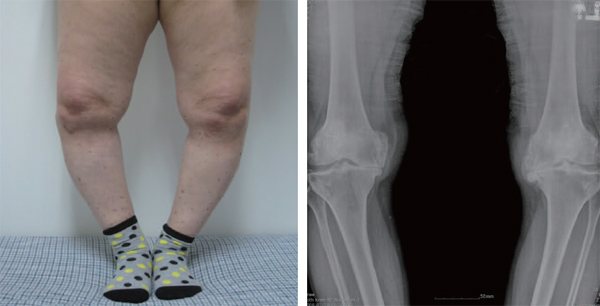

| [건강설계]연골재생술이 능사가 아니다 | |||||

[건강설계]연골재생술이 능사가 아니다 |